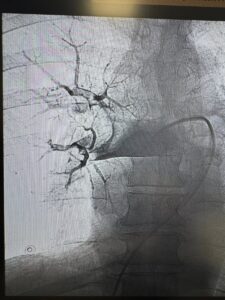

Під рентгенконтролем через судини катетером ми дісталися тромбів й видалили їх спеціальною системою аспірації.

Це перші успішні тромбаспірації при ТЕЛА, виконані у нашому об’єднанні.